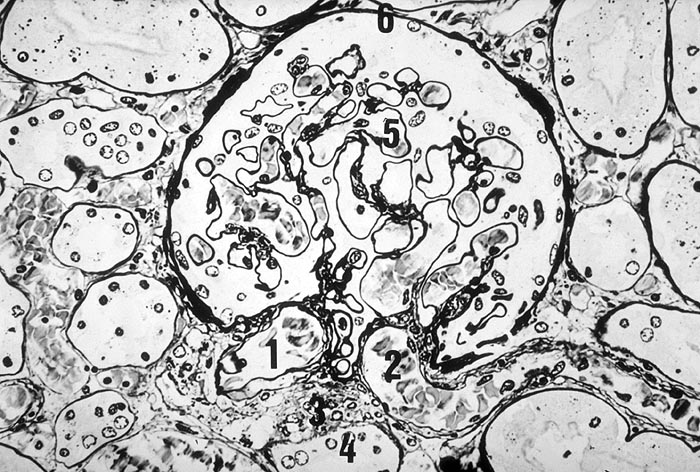

PathoPic ID 1603 - Normaler Glomerulus

Normaler Glomerulus

1. Vas afferens

2. Vas efferens

3. Juxtaglomerulärer Apparat

4. Macula densa

5. Periphere Kapillarschlinge

6. Bowman Kapsel